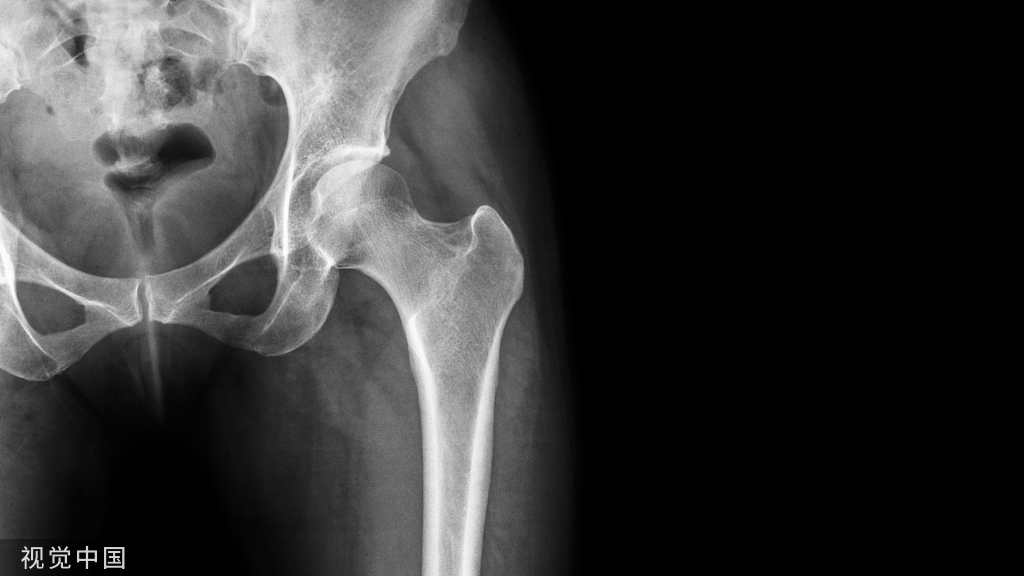

(1)股骨颈骨折

股骨转子间骨折:受伤机制与本病相似,但患者年龄常更大,局部肿胀明显,压痛点在股骨为粗隆部,皮肤一般可见瘀斑;X线片可助鉴别。

(2)股骨转子间骨折

股骨颈骨折:受伤机制与本病类似,但年龄相对较小,局部肿胀及痕斑不甚明显,压痛点在腹股沟中点;X线可助鉴别。

髋关节后脱位:常见于青壮年,有强大暴力损伤史;弹性固定于屈髋、屈膝、内收、内旋位,在臀后可扪及脱出的股骨头;X线片可鉴别。

股骨干上1/3骨折:青壮年及儿童多见,有明显外伤史;局部压痛敏锐,出现短缩、成角或旋转畸形,可触及骨擦感和异常活动;X线片示股骨干骨折。